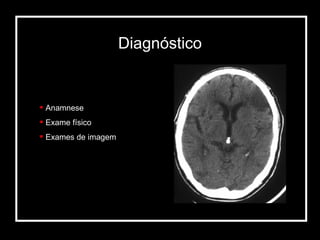

Anamnese Exame físico Exames de imagem Diagnóstico

Anamnese Exame físicoExames de imagem Diagnóstico